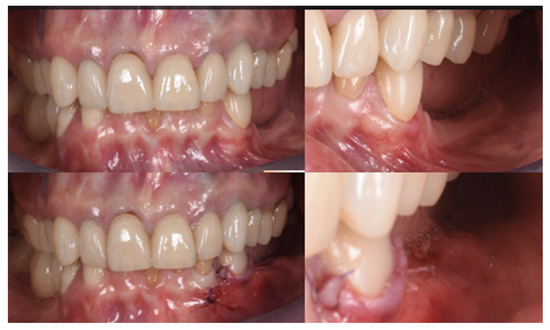

Figure 10.

Clinical evaluation after 18 months of prosthetic loading.